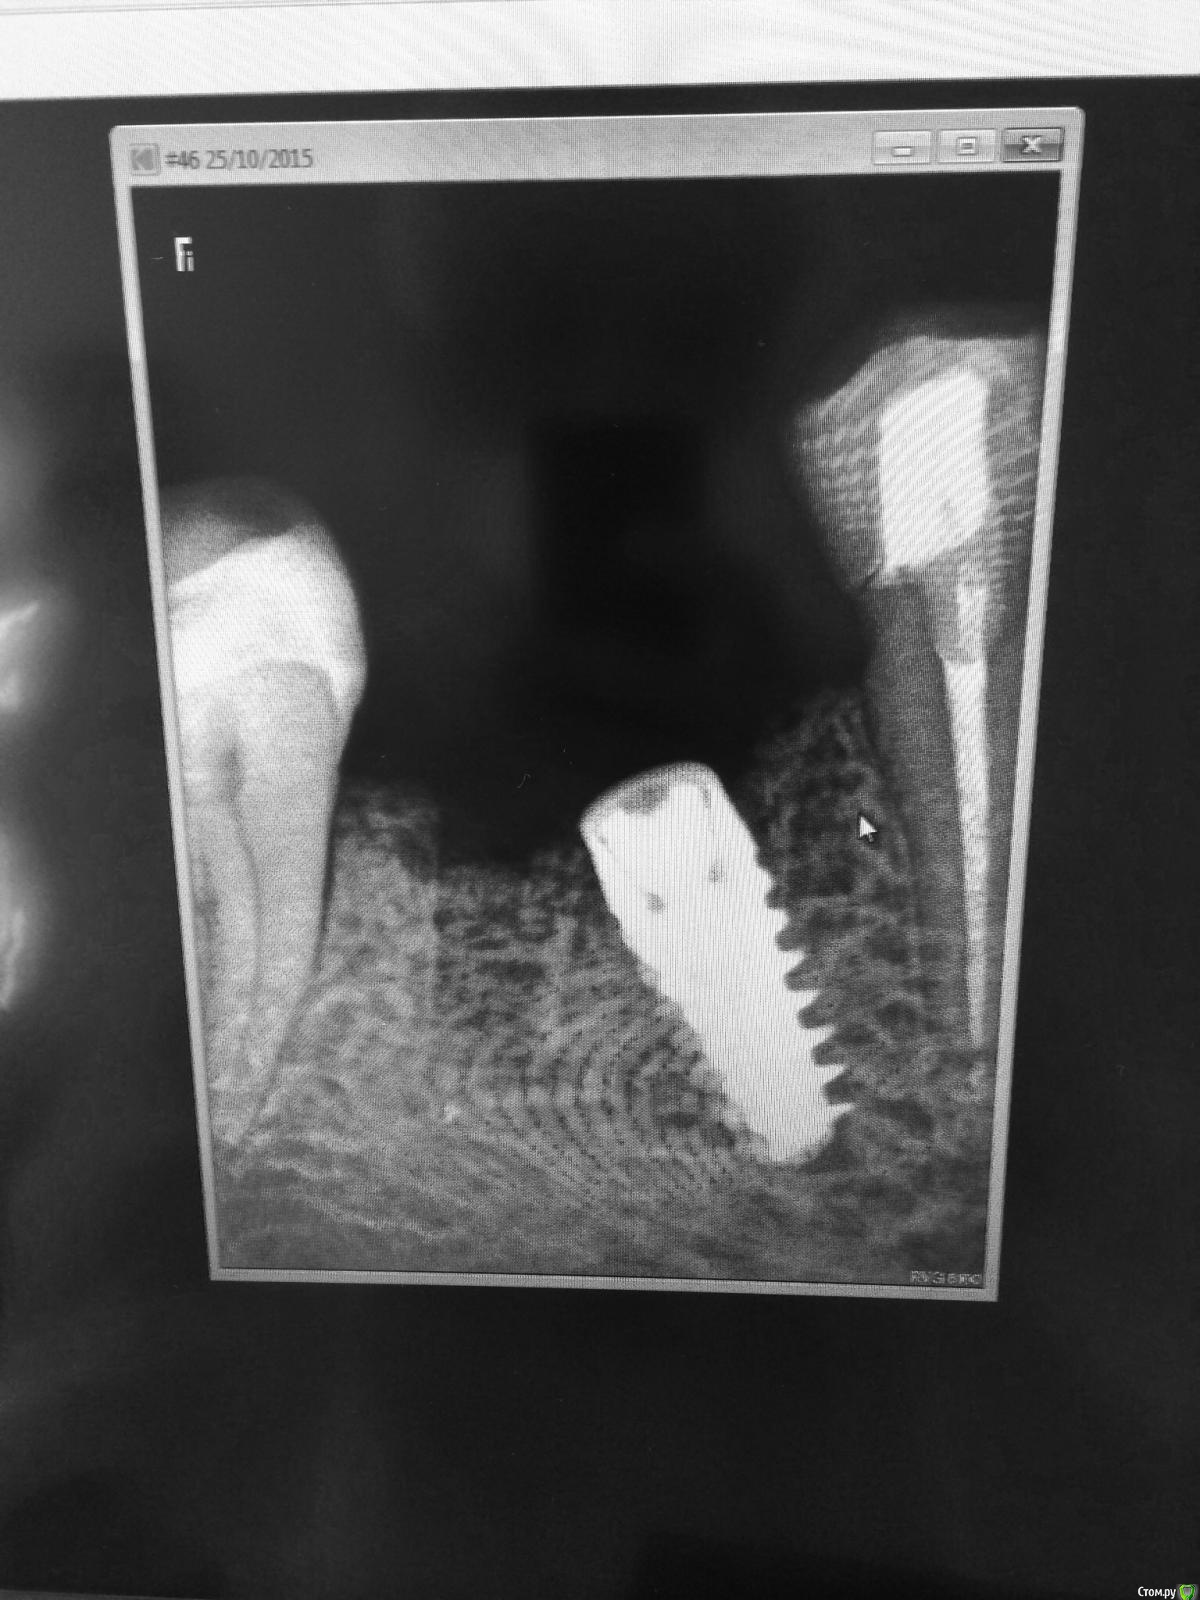

Кариес+ Опубликовано 25 октября, 2015 Автор Поделиться Опубликовано 25 октября, 2015 Уважаемые коллеги , установил имплант, одномоментно сст с бугра. Имплант как видно встал не так как хотел , и имплантовод во время извлечения упал на пол . Переставить вариантов не было. Ушил . Каков ортопедический прогноз ? Имплант нобель актив 4.3/11.5 Ссылка на комментарий

k.t.m. Опубликовано 25 октября, 2015 Поделиться Опубликовано 25 октября, 2015 Угловой стандартный или фрезерный индивидуальный абатмен,позиция больше по глубине плохая ,не заглубили Ссылка на комментарий